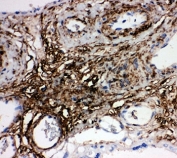

IHC-P: PLTP antibody testing of human placenta tissue